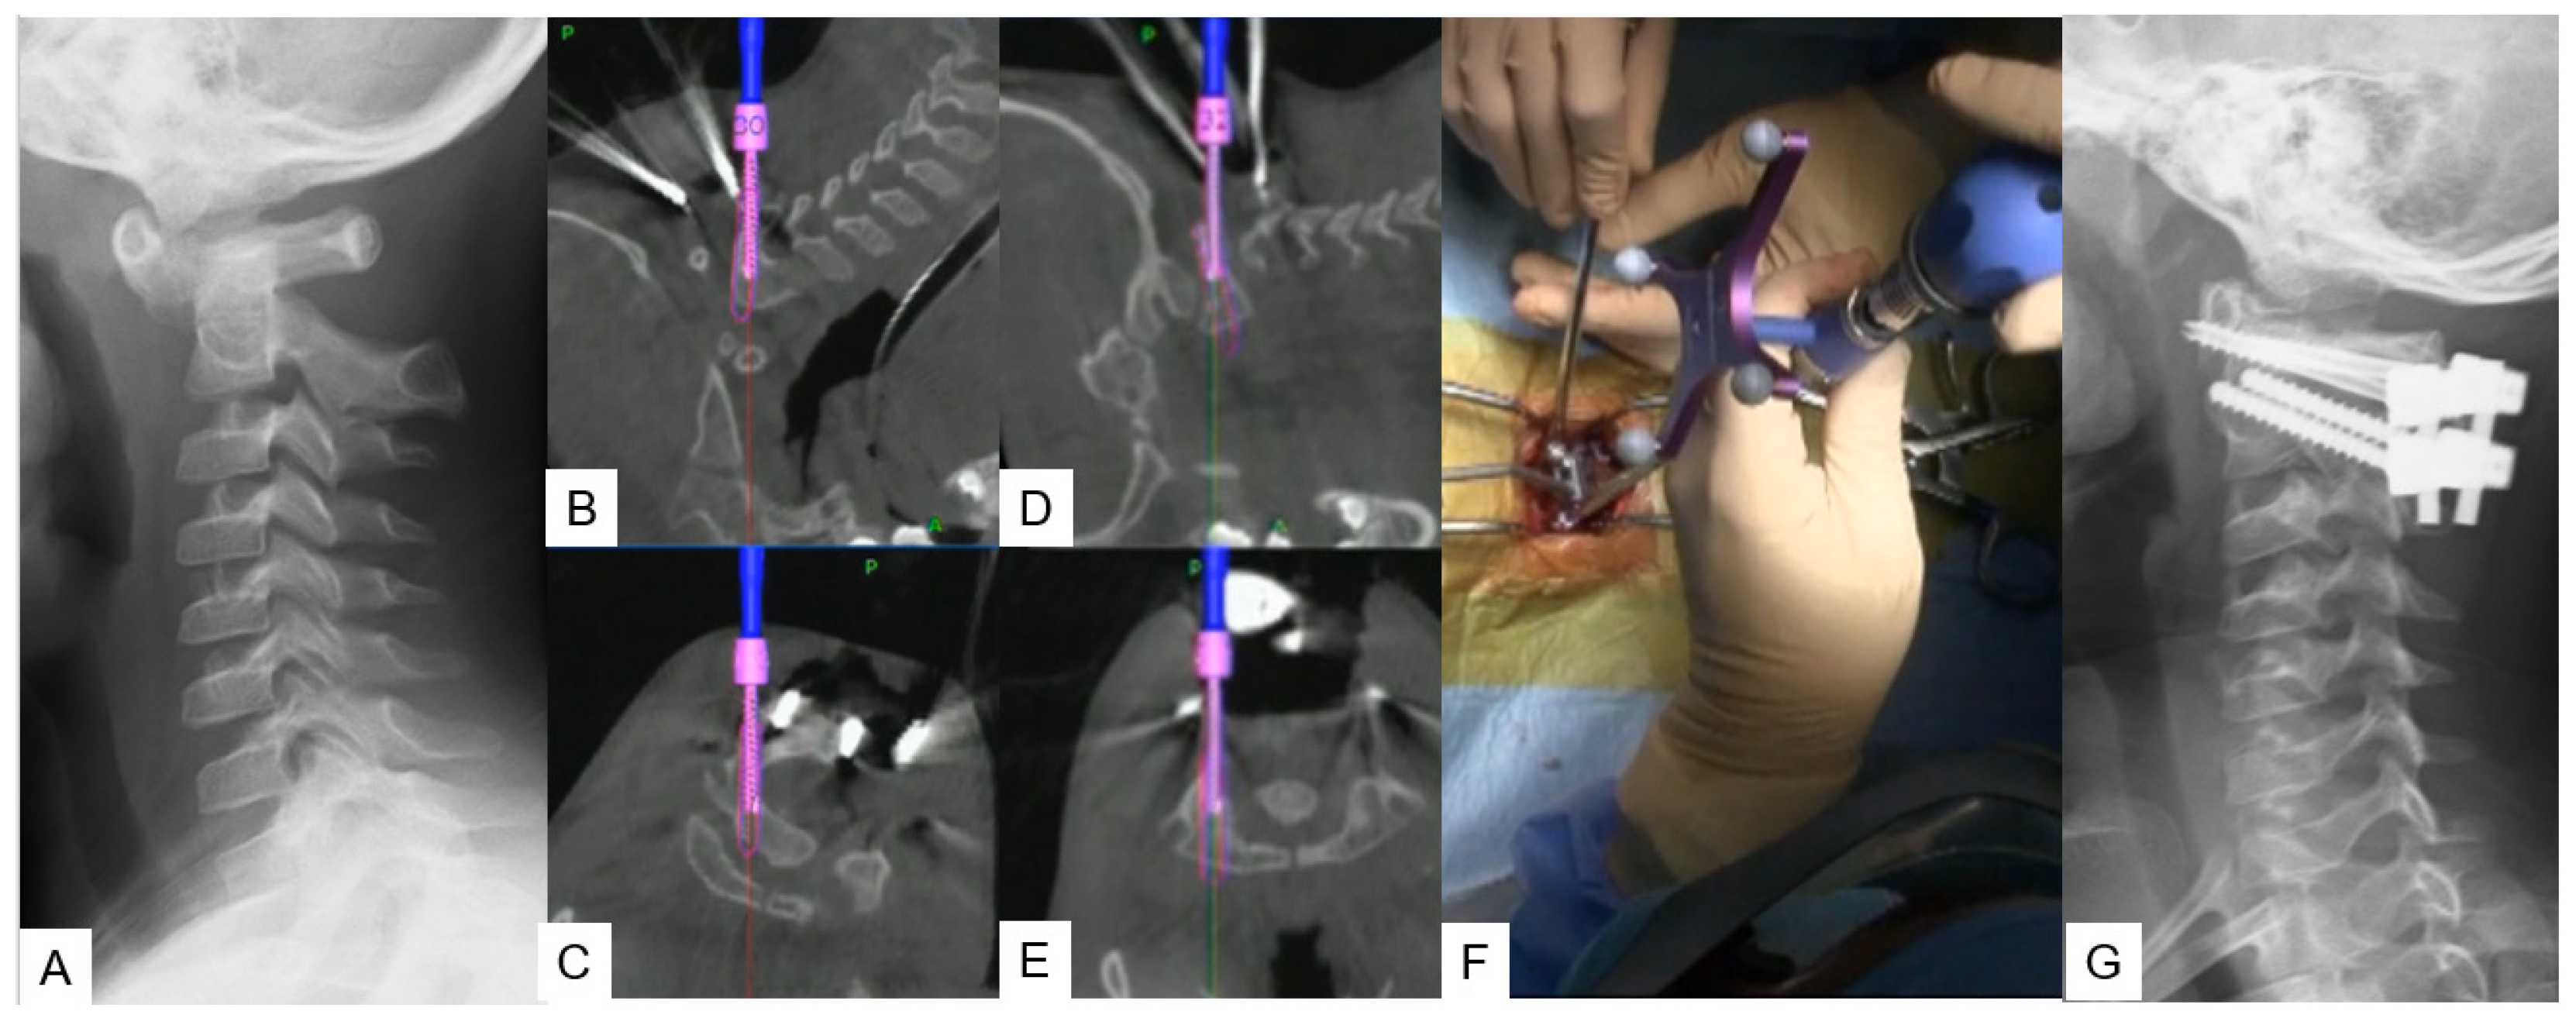

2.2.2. Modified Goel Technique

2.2.3. Midpoint Technique for C1 Lateral Mass Screw (LMS) Placement

- Tanaka, M.; Sonawane, S.; Fujiwara, Y.; Uotani, K.; Arataki, S.; Yamauchi, T.; Ye, Y.; Misawa, H. C-arm Free O-arm Navigated Posterior Atlantoaxial Fixation in Down Syndrome: A Technical Note. Acta Med. Okayama 2022, 76, 71–78. [Google Scholar]